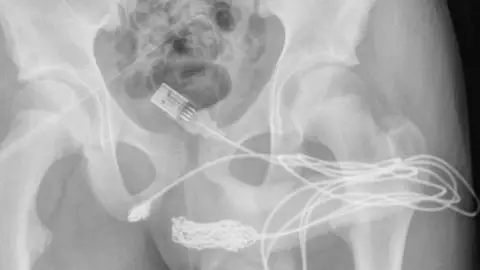

Los estudios de rayos X mostraron que los dos puertos del cable USB habían salido de la uretra, pero que la parte de en medio del cable se encontraba dentro de la uretra y se había enredado, por eso no podía sacarlo.